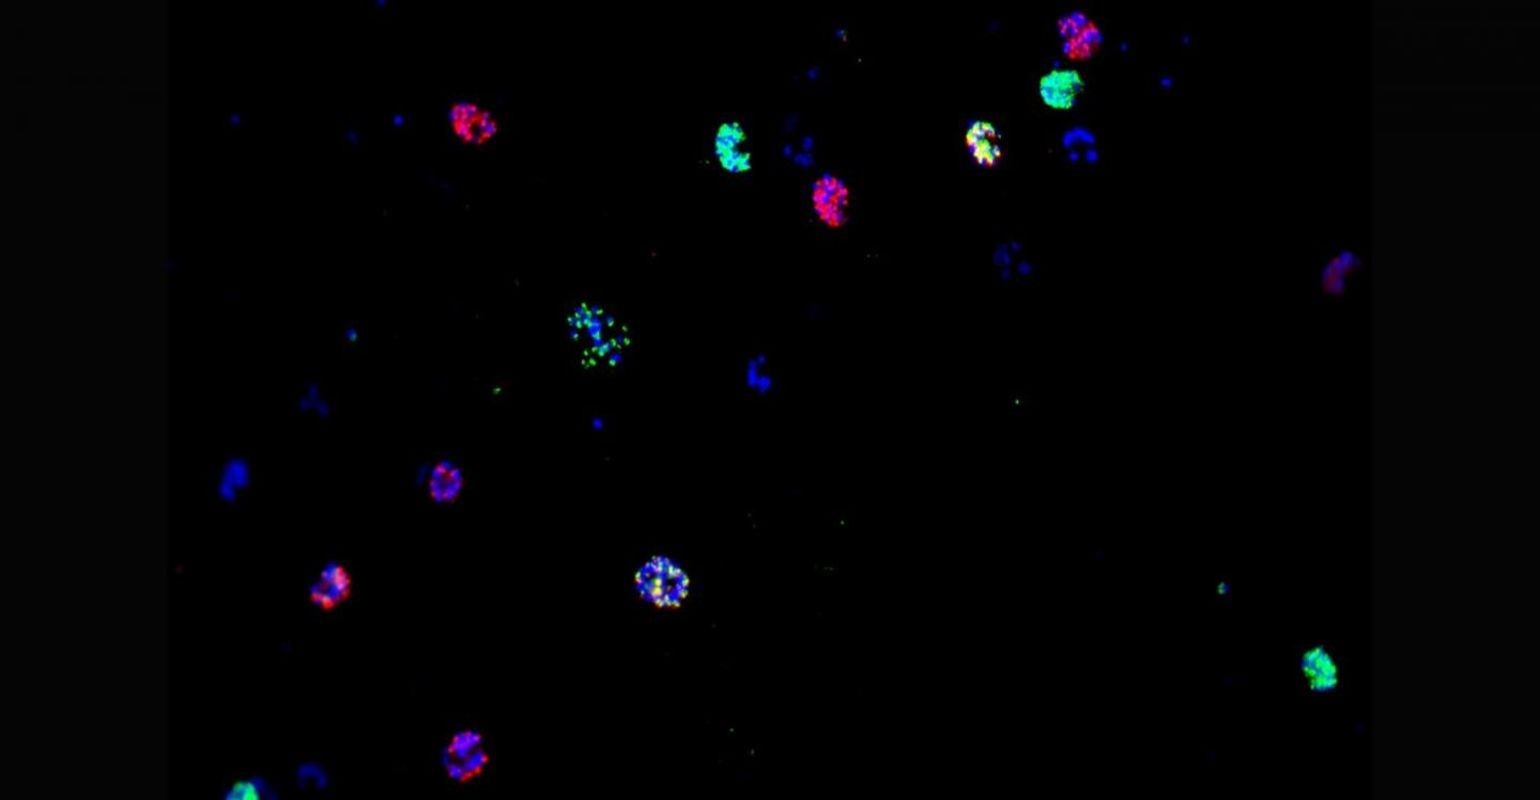

P. falciparum, the most deadly malaria parasite, has developed resistance to all antimalarial drugs, including artemisinin combination therapies (ACTs), which are the current frontline treatment. Most of the known mechanisms by which P. falciparum parasites develop resistance to antimalarial drugs are due to changes in the genome. However, a team led by Alfred Cortés (ISGlobal) and Anna Rosanas-Urgell (ITM) explored the role of epigenetics (i.e. changes in gene expression that do not involve alterations in DNA sequence) in antimalarial drug resistance. Particularly, they looked at two parasite genes -- clag3.1 and clag3.2 -- whose expression is regulated by epigenetic mechanisms and that determine the activity of a channel called Plasmodial Surface Anion Channel (PSAC), which regulates the entry of nutrients and other molecules into red blood cells infected by the parasite. Previously, Cortés and his team had found that switches in the expression of clag3 led to changes in PSAC permeability and resistance to compounds toxic for the parasite.

In this study, the researchers investigated whether other antimalarial drugs require clag3 to reach their intracellular target and could consequently be prone to parasite resistance by epigenetic mechanisms. They found that certain compounds such as bis-thiazolium salts T3 and T16 require the product of clag3 genes to enter infected erythrocytes. Furthermore, P. falciparum populations could develop resistance to these compounds through the selection of parasites with reduced expression of both genes. In contrast, other compounds predicted to use transport pathways to enter infected erythrocytes, such as doxycycline, azithromycin or lumefantrine, did not require expression of clag3 genes for their anti-malarial activity.